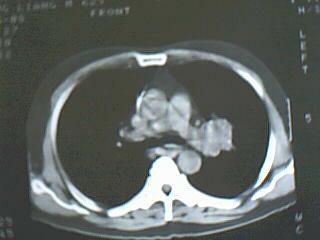

中央型肺癌

左侧中央型肺癌伴阻塞性肺炎

支持:左侧中央型肺癌伴阻塞性肺炎

左侧中央型肺癌并阻塞性肺炎。